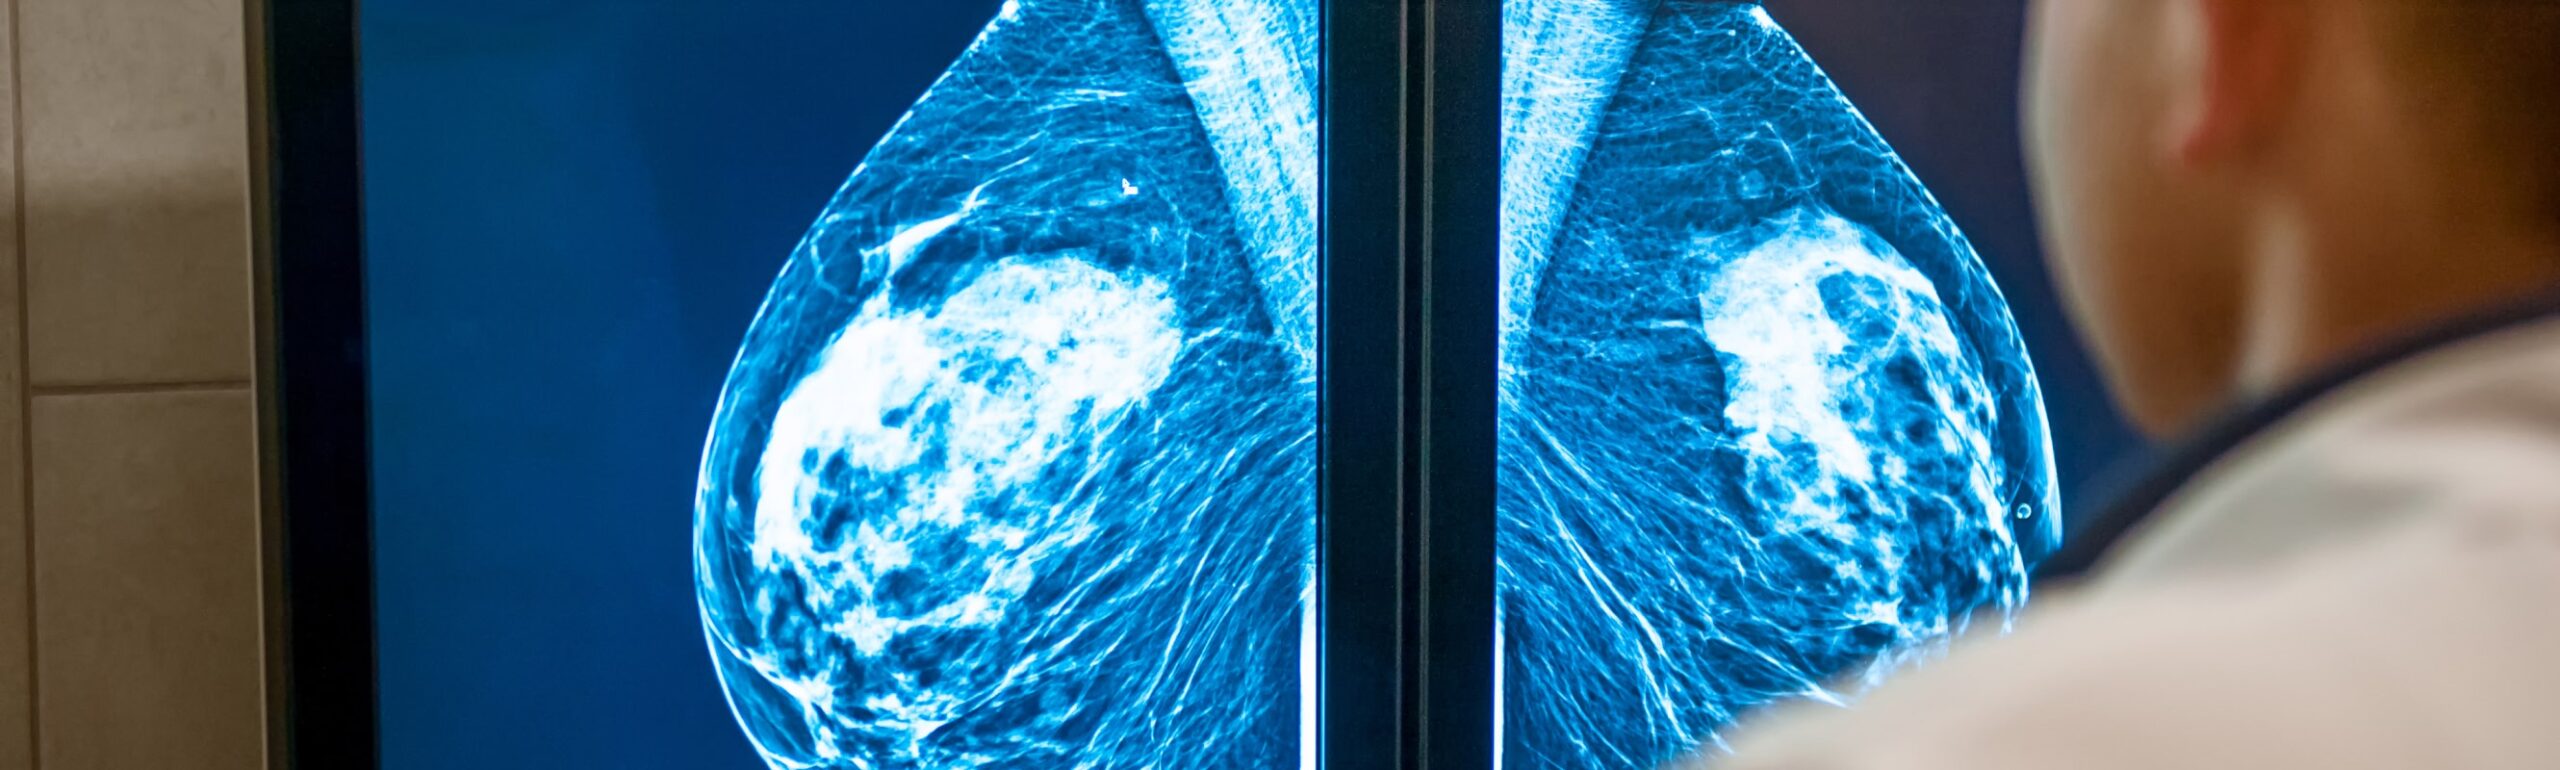

Mastectomie prophylactique : pour qui et pourquoi ?

La mastectomie prophylactique, aussi appelée mastectomie de réduction de risque, est une chirurgie préventive du sein visant à diminuer considérablement le risque de développer un cancer. Bien qu’il s’agisse d’une intervention lourde, elle représente pour certaines femmes une véritable assurance de longévité et de sérénité face à une prédisposition génétique importante. Cette démarche, souvent associée aux mutations des gènes BRCA1 et BRCA2, PALB2 est encadrée par des critères médicaux précis et une réflexion approfondie accompagnée par une équipe pluridisciplinaire.

Pour les femmes à haut risque génétique, la mastectomie prophylactique est aujourd’hui la mesure de prévention la plus efficace. Contrairement au suivi renforcé (IRM et mammographie annuelle), elle agit directement sur la cause anatomique : le tissu mammaire susceptible de développer des cellules cancéreuses est retiré.